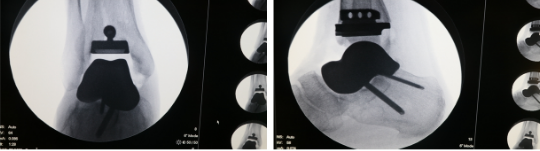

手术由山东大学第二医院手外科/足踝外科胡勇、曹松华主刀,在麻醉科和第二手术部的密切配合下,团队为王某彻底清理了坏死的距骨及周围炎性组织,置入3D打印距骨假体试模,合适后,植入生物型3D打印假体,用螺钉将距骨固定到跟骨上。再于胫骨远端用3D打印导板截骨,截骨后装入试模,最后置入合适的胫骨踝关节假体,手术顺利完成。3D打印胫骨截骨导板的使用大大缩短了手术时间、增加了截骨精准度、减少了透视造成的辐射损害。